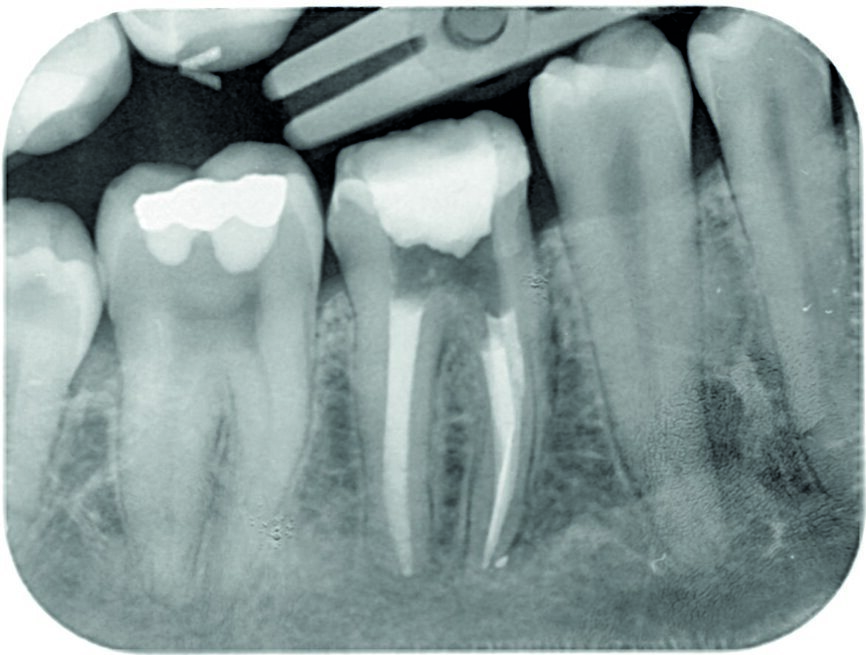

Based on the clinical and radiographic findings, root canal therapy was initiated. A rubber dam was placed and the tooth was accessed without the need for an aesthesia. Crown-down preparation was performed for orthograde endodontic treatment. The mesiobuccal canal was negotiated with a size 0.06 C-file and the separated instrument was removed under magnification with a dental operating microscope (16 ×, Zeiss), and a control radiograph was taken (Fig. 2). The root canals were cleaned and shaped with ProTaper rotary instruments (Dentsply Maillefer). The mesial canals were prepared up to F3. All of the canals were irrigated with a copious amount of 5.25% sodium hypochlorite and 17% EDTA. This was followed by irrigation with 0.9% saline to remove any remnants of hypochlorite and EDTA. Haemorrhage and exudate from the apical region of the distal canal were observed during the instrumentation, which suggested resorption exteriorisation. The canals were dried with absorbent paper points, and calcium hydroxide paste (ApexCal, Ivoclar Vivadent) was placed in the canals as an intracanal medicament, followed by temporary restoration with glass ionomer cement.

Fig. 2: Control radiograph to assess the removal of a separated lentulo